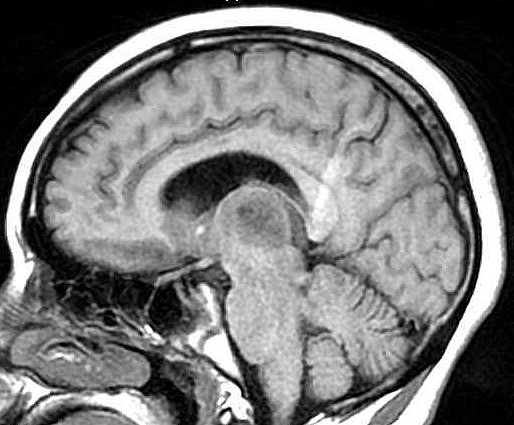

| Fem. 17a. |

| Nódulo sólido homogêneo preenchendo o III ventrículo, com limites precisos, com hipossinal em T1 e hipersinal em T2 e FLAIR, que se impregna por contraste paramagnético. Lesão menor implantada no assoalho do IV ventrículo provavelmente representa disseminação por via liquórica. |

| SAGITAIS, T1 SEM CONTRASTE | T1 COM CONTRASTE | |

| F. 17a. Tumor teratóide rabdóide atípico de III ventrículo. RM | HE | VIM, GFAP | HHF35, desmina, 1A4 | AE1AE3, EMA |